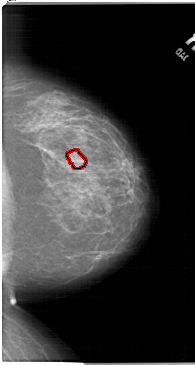

A_1515_1.RIGHT_MLO

RIGHT_MLO LINES 6406 PIXELS_PER_LINE 3451 BITS_PER_PIXEL 12 RESOLUTION 43.5 OVERLAY

FILE: A_1515_1.RIGHT_MLO.OVERLAY

TOTAL_ABNORMALITIES 1

ABNORMALITY 1

LESION_TYPE MASS SHAPE LOBULATED MARGINS ILL_DEFINED

ASSESSMENT 4

SUBTLETY 2

PATHOLOGY BENIGN

TOTAL_OUTLINES 1

BOUNDARY